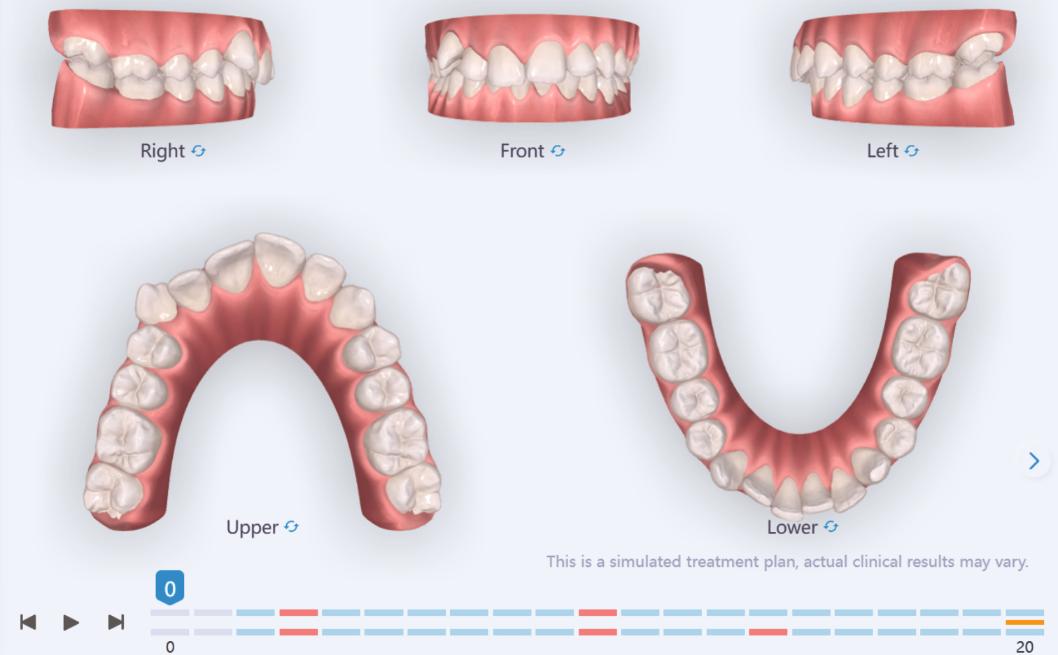

We approached the case by combining upper distalization using the A8 protocol with an asymmetric virtual jump. In this way, we solved the crowding without proinclining the incisors and improved the anteroposterior relationship through the use of elastics. In the lower arch, we carry out a development of the posterior sectors prior to the resolution of the crowding, in order to avoid roundtripping and excessive IPR of the incisors. To achieve an effective extrusion and distalization of 13, we combine the use of direct bonding button on vestibular of 13, with angelButton elastics mesial and distal to the canine. These mechanics help to ensure that the extrusion is real and that the aligner always remains adapted.

Treatment details

In the upper arch, the main goal will be to correct the Class II malocclusion by distalizing the upper posterior teeth in order to resolve crowding without proinclining the incisors. This movement will be accompanied by an asymmetric “bite jump” of 1 mm, which will help improve the skeletal Class II discrepancy, promoting mandibular projection, especially considering that the patient is still in the growth phase. Additionally, bilateral and symmetric expansion will be planned until a torque of 0° is achieved, allowing for proper transverse alignment and greater stability of the final result. Lingual button cutouts will be placed on teeth 14 and 24 to facilitate the required movements. To optimize control and retention, vertical mesial beveled attachments, as large as possible, will be placed on the premolars and molars, as well as on teeth 12 and 22, reinforcing the mechanics in the anterior sector. The inclination of the central incisors 11 and 21 will be corrected according to the visual reference provided in the clinical image. Furthermore, it will be necessary to center the upper midline by shifting it 0.5 mm to the left to achieve greater aesthetic symmetry. As for the lower arch, treatment will begin with a phase of expansion and derotation of the posterior teeth, which will set the stage for subsequent movements in the anterior sector. Once this goal is achieved, alignment of the teeth from canine to canine will proceed, aiming to minimize anterior interproximal reduction (IPR) and avoid unnecessary round- tripping movements of the incisors. Vestibular button cutouts will be made on teeth 36 and 46, while teeth 37 and 47 will have horizontal attachments that will serve as anchorage to ensure stability during treatment.

Treatment setup